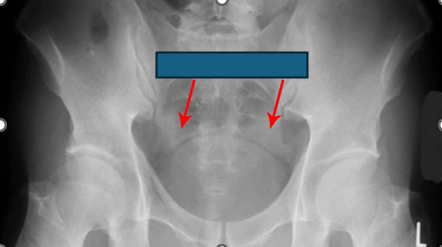

This radiological sign (depicted here) represents the presence of fluid or blood in the pelvic peritoneal recess on supine abdominal radiography.

Dog’s Ear Sign

The appearance of the sign comes from a convex soft-tissue density representing fluid or blood in the lateral pelvic peritoneal recess separated from the bladder by a thin hyperlucent strip of extraperitoneal fat which is reminiscent of dog ears.